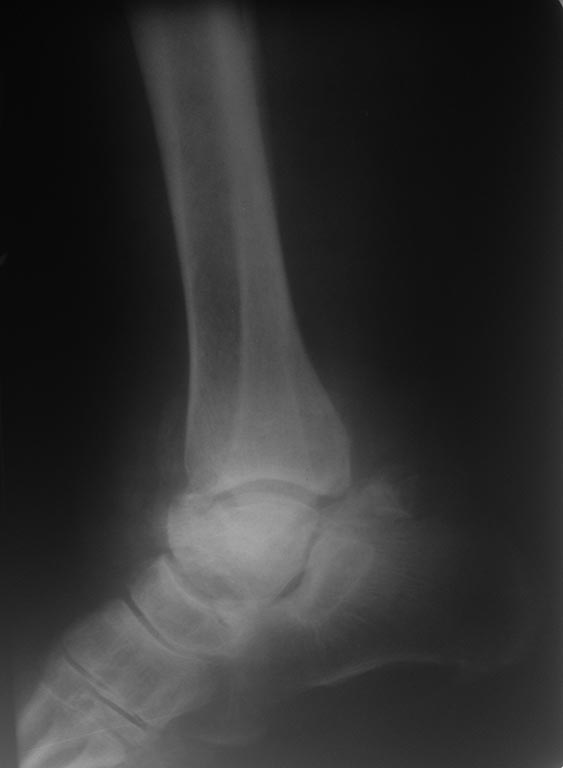

[Ortho] Перелом таранной кости

Имя     : IMG_1499.JPG